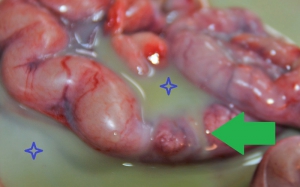

下の写真は、子宮蓄膿症の最悪を極める例のひとつです。発見が遅れたり、来院するまでに時間がかかってしまい、不幸にもお腹の中で子宮に穴が開いてしまった子宮蓄膿症です。(子宮から漏れた膿の状況をよくご理解いただくためにあえて画像調整をしておりません。)

膿が緑矢印のところから漏れ出ています。青星印で示した全体に「緑色の膿」が一面に溢れているのがお分かりかと思いますが、子宮が破れて間もない状態でしたので、このワンちゃんは「緊急の手術」でなんとか一命をとりとめました。

子宮破裂は、致死性腹膜炎を生じて処置が遅れれば必ず死に至ります。このような状況下での手術はより長時間となり、死亡率も非常に高くなります。さらに、腹膜炎の治療のために膿を排泄するためのドレナージを要するため、数日間はお腹を閉じることができません。膿がお腹から排泄されたら、再度お腹を縫う手術を行う必要があります。